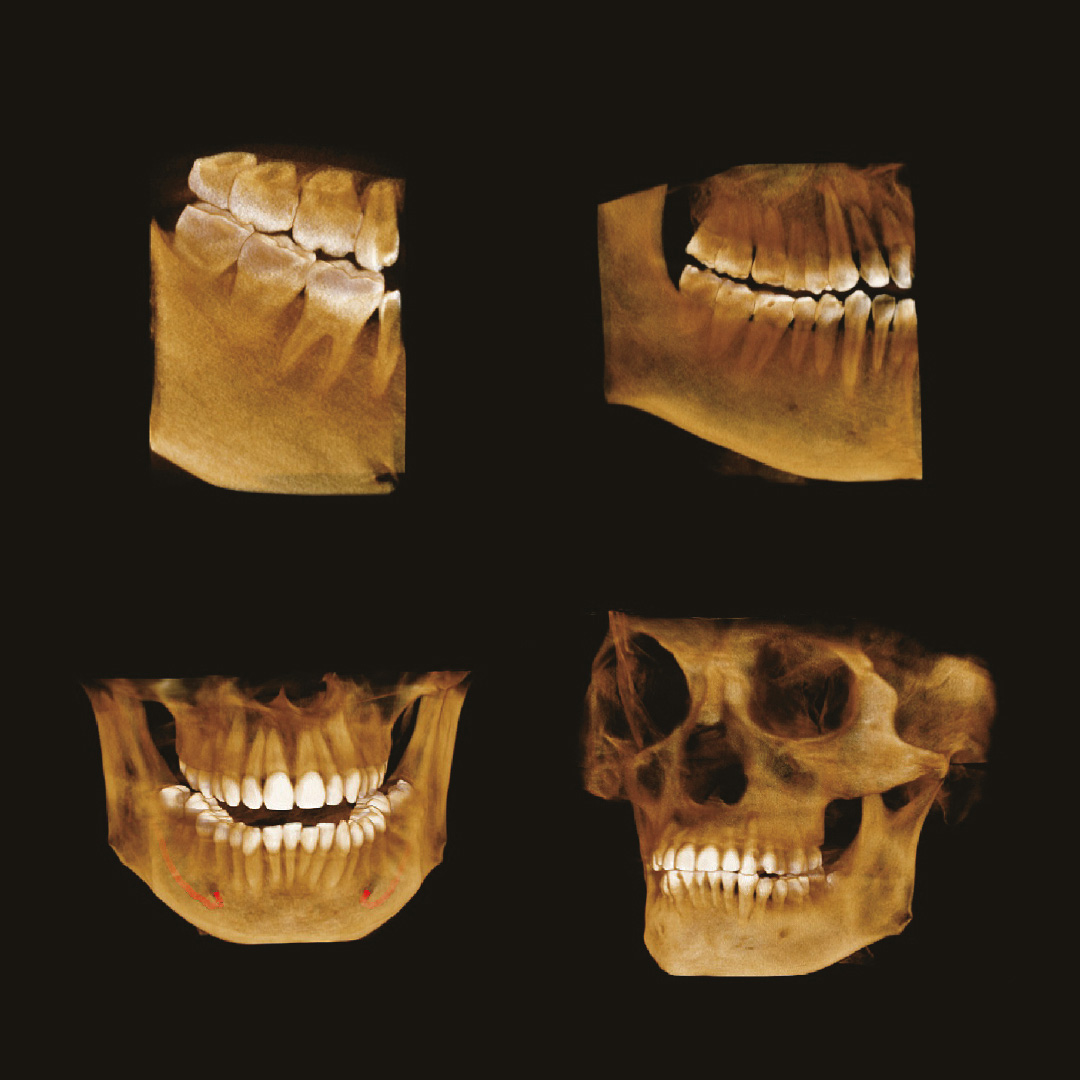

Современная стоматология уже давно не работает вслепую, и каждому из направлений стоматологии необходимо проводить рентгеновские исследования:

• Стоматолог-терапевт по снимку видит не только кариес, а также способен оценить, как периодонтальные ткани, так и различные воспалительные процессы затрагивающие пульпарную камеру.

• Стоматолог-хирург не способен производить свои манипуляции без снимка КТ, иначе он будет вынужден действовать вслепую, не сумев оценить анатомию области вмешательства.

• Стоматолог-ортопед не сможет гарантировать надежность конструкции без правильной оценки стабильности опорных зубов при помощи снимка КТ.

• Стоматологу-ортодонту, чтобы правильно простроить план лечения, помимо слепков, так же нужен снимок КТ.